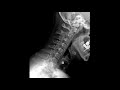

Что лучше, Плаквенил или Иммард при ревматоидном артрите? Ответ на этот вопрос зависит от индивидуальных особенностей больного и рекомендаций врача. Плаквенил (хлорохин) и Иммард (лефлуномид) являются препаратами, используемыми в лечении ревматоидного артрита.

Плаквенил обладает противовоспалительным и иммуномодулирующим действием. Он может помочь контролировать симптомы ревматоидного артрита, такие как болезненность, воспаление и отечность суставов. Однако, его эффективность и безопасность могут варьироваться в зависимости от пациента.

Иммард также применяется для снижения воспаления и симптомов ревматоидного артрита. Он может замедлить прогрессирование заболевания, улучшить функциональность суставов и снизить потребность в других противовоспалительных препаратах. Однако, как и с Плаквенилом, результаты могут различаться у пациентов.

Выбор между Плаквенилом и Иммардом должен осуществляться врачом, исходя из симптомов, истории болезни и других факторов каждого конкретного больного. Консультация с ревматологом является необходимым условием для определения наиболее подходящего препарата и плана лечения при ревматоидном артрите.